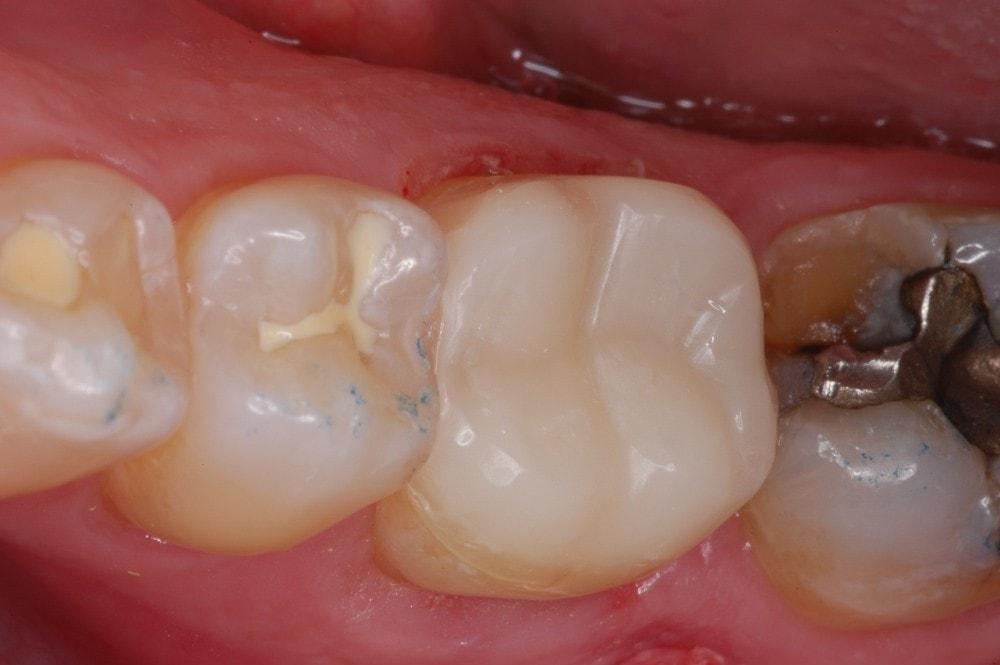

Managing fractured marginal ridge

Ribbond will not stop a tooth from fracturing but Ribbond can divert forces side ways. As a result, the tooth fractures laterally. A lateral fracture increase the odds the tooth can be restored. A vertical fracture is catastrophic.

Connect